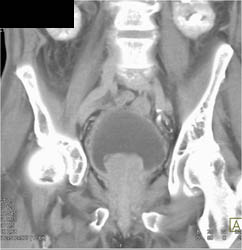

Bladder Cancer